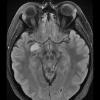

NEOPLASMS (GLIAL)

Astrocytoma, IDH-mutant, WHO Grade 2 (10)